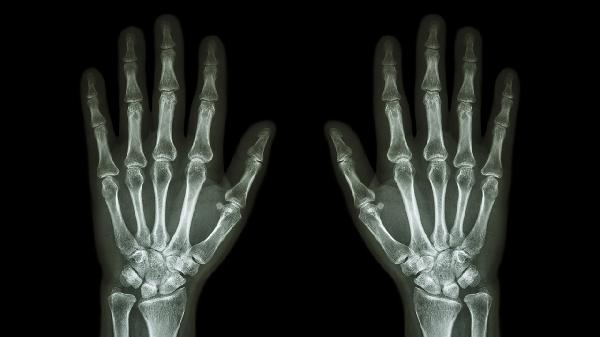

缺鈣可能導致手指關節(jié)疼痛,但并非唯一原因。手指關節(jié)疼痛可能與鈣代謝異常、骨關節(jié)炎、類風濕關節(jié)炎、痛風、外傷等因素有關。缺鈣引起的關節(jié)疼痛通常伴隨骨質疏松、肌肉痙攣等癥狀。

鈣是維持骨骼健康的重要礦物質,長期缺鈣可能導致骨質疏松,增加骨骼脆弱性,進而引發(fā)關節(jié)疼痛。缺鈣還可能影響神經(jīng)肌肉功能,導致肌肉痙攣或抽搐,間接引起關節(jié)不適。這類疼痛多表現(xiàn)為隱痛或鈍痛,活動后可能加重,補鈣后癥狀可能緩解。

手指關節(jié)疼痛更多由其他疾病引起。骨關節(jié)炎常見于中老年人,表現(xiàn)為關節(jié)僵硬和活動受限。類風濕關節(jié)炎屬于自身免疫性疾病,多伴隨晨僵和對稱性關節(jié)腫痛。痛風由尿酸結晶沉積引發(fā),疼痛劇烈且突發(fā)。外傷或過度使用手指也可能導致關節(jié)疼痛,通常有明確誘因。

若出現(xiàn)持續(xù)手指關節(jié)疼痛,建議就醫(yī)檢查血鈣、維生素D水平及關節(jié)影像學評估。日??蛇m量增加奶制品、豆制品、深綠色蔬菜等富含鈣的食物攝入,避免過度勞累或手指重復性動作。適度曬太陽有助于促進維生素D合成,幫助鈣吸收。